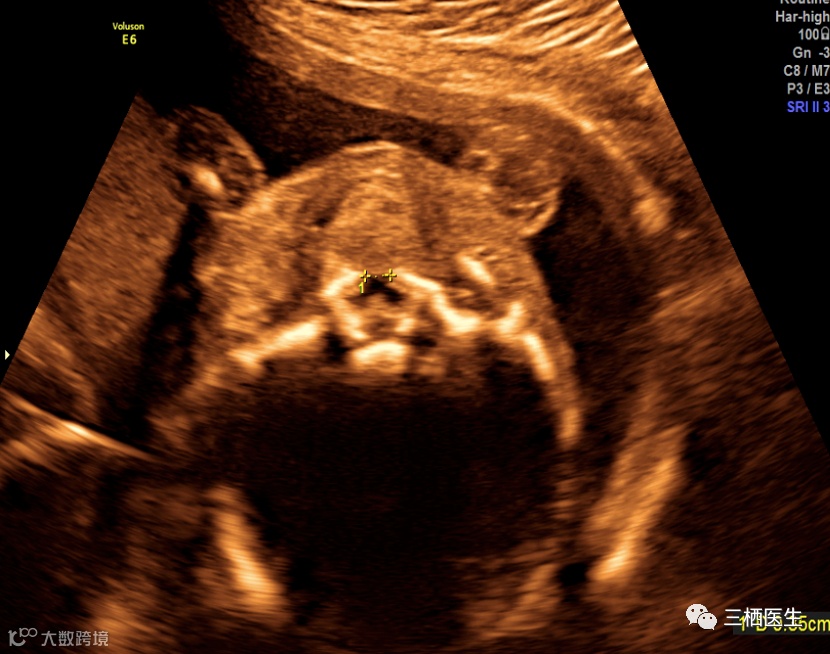

病例:孕妇32y,G2P1,孕20+周,无特殊家族史,常规排畸超声如下发现:

上唇线及牙槽骨连续

超声诊断:继发腭裂(软腭及硬腭裂)。